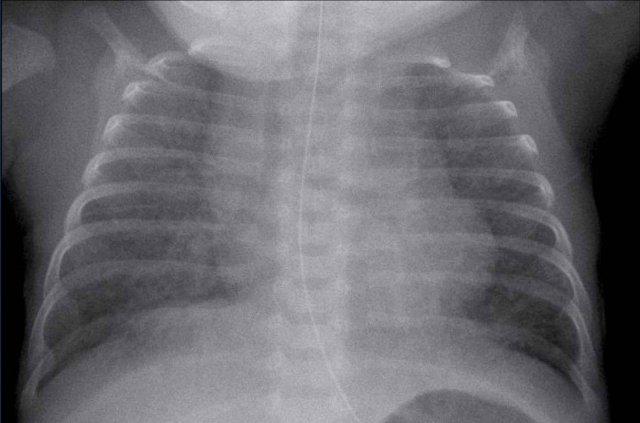

Trẻ sơ sinh đủ tháng, có suy hô hấp sau 24 giờ.

Hình ảnh

Ứ khí quá mức cả hai phổi và tim to với tăng đậm các nét kẽ và các nét mạch máu. Không có tràn dịch màng phổi.

Chẩn đoán phân biệt bao gồm thở nhanh thoáng qua ở trẻ sơ sinh và viêm phổi sơ sinh. Sau 48 giờ, tình trạng suy hô hấp không cải thiện, và trẻ sơ sinh xuất hiện các dấu hiệu nhiễm trùng.

Người ta

có thể lập luận rằng có thể có sự kết hợp giữa TTN và viêm phổi.